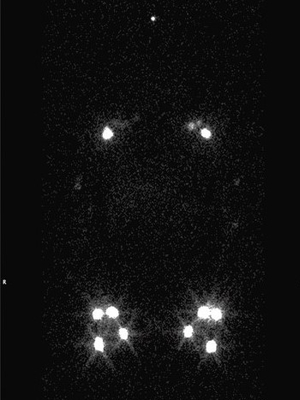

lymphoscintigraphy

SPECT CT

SPECT/CT Lymphoscintigraphy:  SPECT/CT stands for single-photon-emission computed tomography. This scan consists of combining a CT scan (which lets us see your anatomy clearly) with a scan that tracks the progression of a tracer through that anatomy over a certain period of time. It lets us see the volunteer's anatomy with clarity as the tracer moves through.